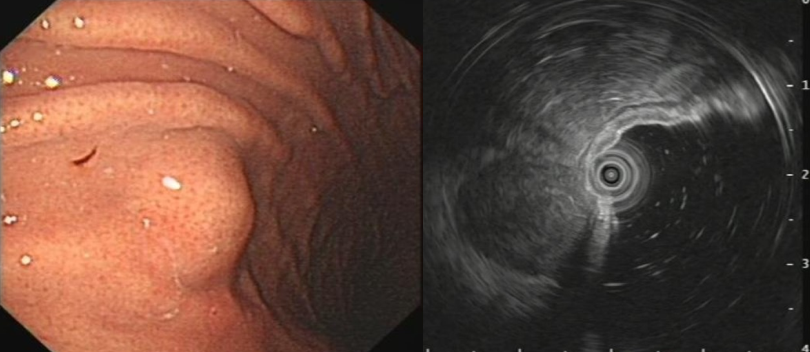

王女士,52岁,胃镜检查发现胃底1.0x1.2cm间质瘤,超 - 抖音

图片尺寸1920x1440